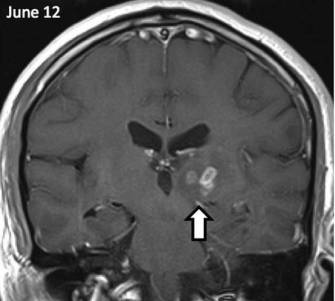

Ez az első alkalom a férfi megfordult, hogy az orvosok négy évvel ezelőtt, ő fejfájásra panaszkodott, és furcsa szagot. Az orvosok, akik végzett felmérés, megzavarodtak kóros területeket az agyban, hogy az MRI kimutatta. Megfigyelések a következő években azt mutatta, hogy a rendellenesség által mozgatott öt centiméter, írja a The Guardian.

Az orvosok a St. Thomas Kórház beteg HIV-tesztet, a szifilisz és a különböző fertőző betegségek. Ennek eredményeként, a biopszia jelenlétét mutatta galandféreg. Genetikai Wellcome Trust Sanger Institute Cambridge megállapítottuk, hogy ez egy rendkívül ritka parazita ismert Spirometra erinaceieuropaei.